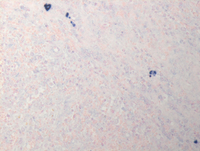

CD20 and CD79a IHC

As a result of anti--CD20 therapy, CD20 immunostain (first image) is negative. However CD79a immunostain is strongly positive in all receptors at low power as well as that high-power confirming B-cell lineage.